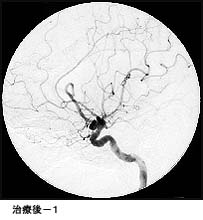

破裂脳動脈瘤に対するコイル塞栓術GODコイルだとちょっと古いので、コイル塞栓術とする方が良いのではないかと思います。

術後 コイルにより動脈瘤が写らなくなりました。